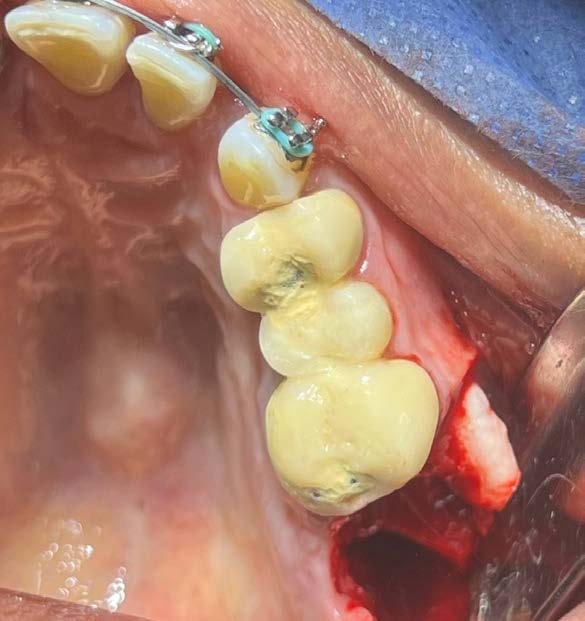

Por lo que se propone procedimiento quirúrgico con la evidente comunicación oroantral al realizar las extracciones de los órganos dentales involucrados. Previa asepsia y antisepsia, colocación de campos estériles, extracción de segundo y tercer molar superior derecho e incisión envolvente con descarga mesial (Figura 3), rotación y afronte mediante puntos simples de la bola adiposa de Bichat para el cierre de la comunicación oroantral (Figura 4), farmacoterapia con base en amoxicilina con ácido clavulánico. Una semana después refiere no presentar rinorrea y mejoría al 100% de la obstrucción. Posterior a 6 meses de evolución clínica (Figura 5) y radiográficamente (Figura 6), no se observa comunicación oroantral o paso de líquidos de la cavidad oral a la cavidad nasal.

4. Cierre de comunicación con la bola adiposa de Bichat.

Figura 3. Colgajo envolvente con liberatriz mesial y alveolo postextracción.

En particular, en cuanto a la prevención de recurrencias por comunicación oroantral, el cierre con la bola grasa de Bichat parece ser especialmente adecuado por su alta tasa de éxito y un procedimiento técnicamente sencillo debido a su gran versatilidad, fácil movilización, acceso y alta nutrición debido a su rica vascularización, ayuda a evitar la dehiscencia de la sutura y baja tasa de complicaciones especialmente en los casos en que se requiere un cierre quirúrgico sin tensión, así como la conservación de la estructura mucosa y con ello la pérdida de la

profundidad del vestíbulo, bajo riesgo de infección, posibilidad de reposición del colgajo y sin cicatriz visible evitando con todo esto el fracaso del procedimiento.22